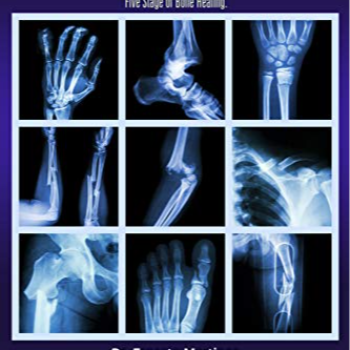

This is where Radhakrishna Hospital enters Ramesh's story, offering a beacon of hope with their specialized treatment for all types of bone fractures. Known for its comprehensive approach, the hospital doesn’t just focus on the physical healing process but understands the emotional and practical hurdles that accompany such injuries.

The first step in Ramesh's recovery was a thorough diagnosis. Using advanced imaging technologies, the specialists at Radhakrishna Hospital assessed the extent of Ramesh’s injury. The goal was not just to mend the bone but to ensure a full recovery that would allow Ramesh to return to his life and responsibilities.